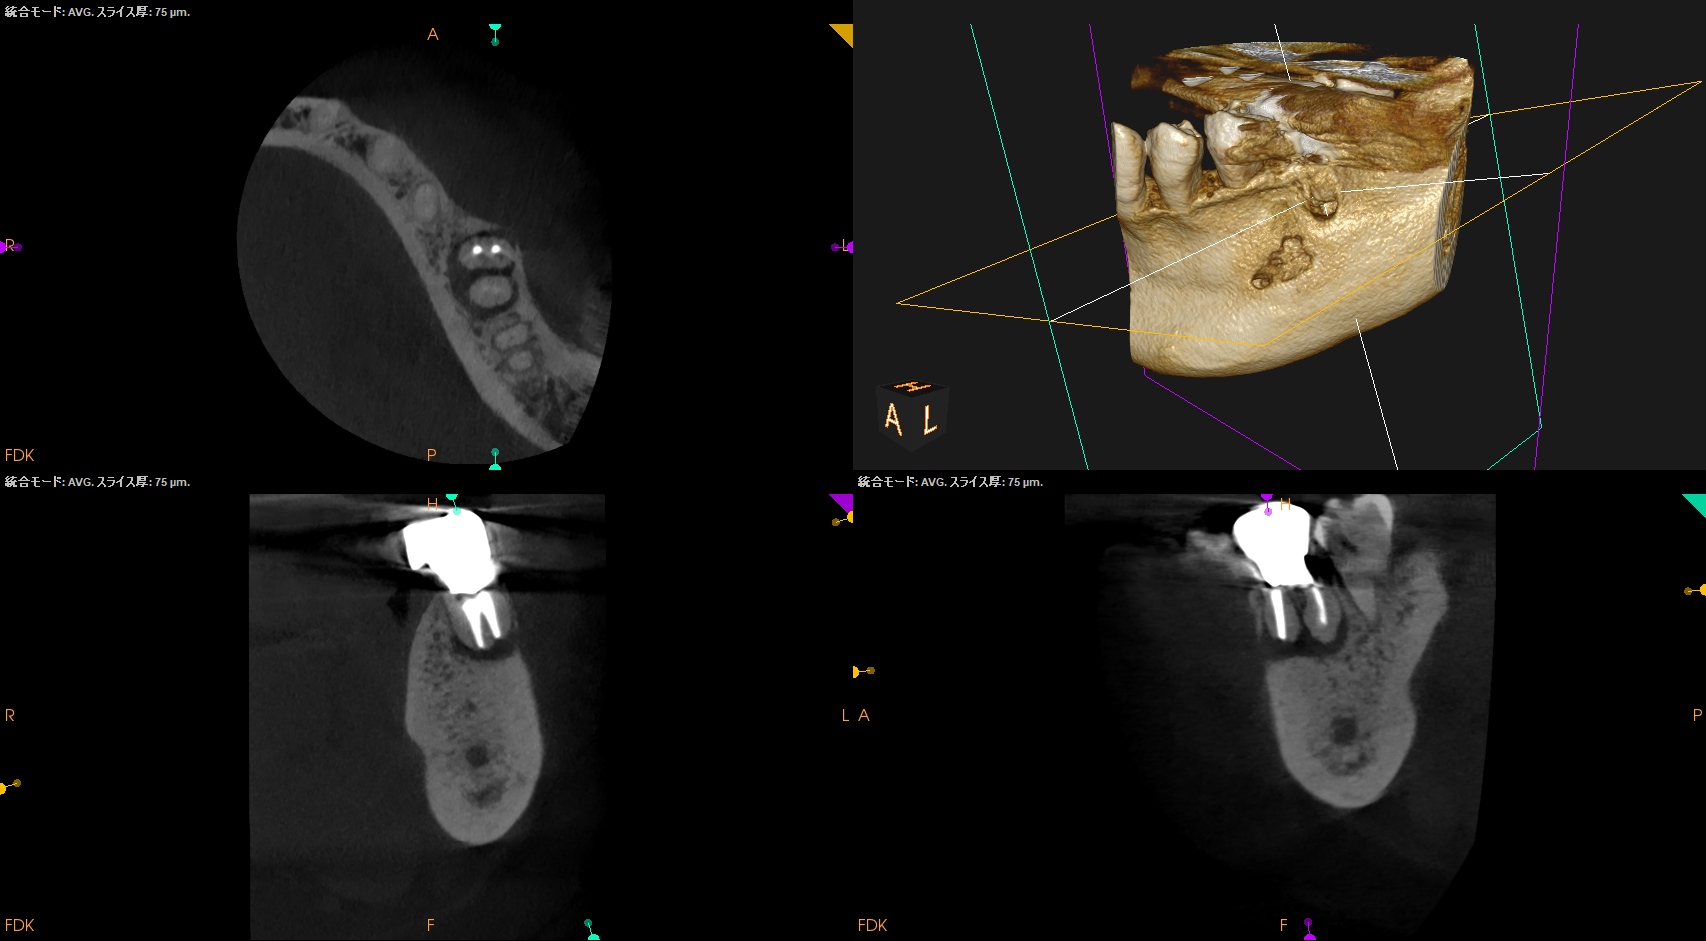

CBCT(2024.9.12)

MB

ML

D